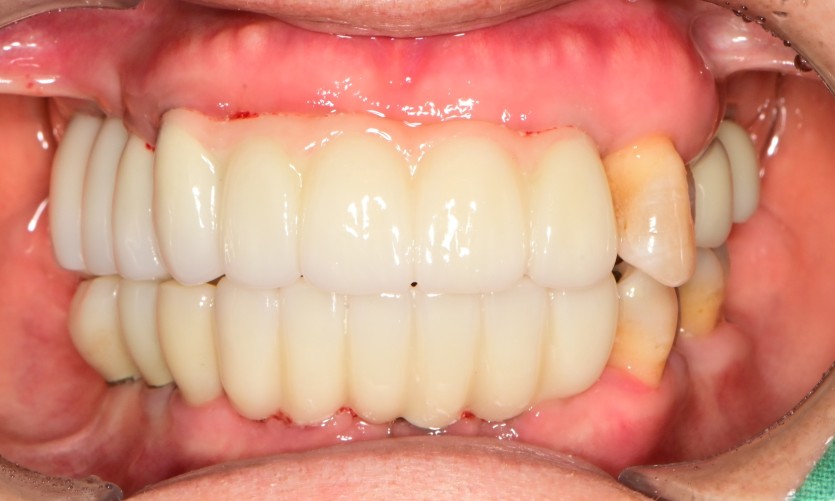

만 56세 상 하악 임플란트 증례

상 하악 임플란트 증례입니다.

12개의 임플란트로 완성하였습니다.

(상악 6개, 하악 6개)